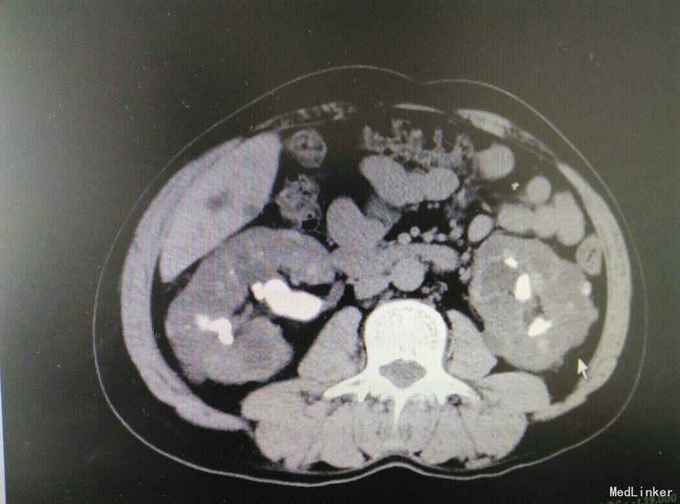

多囊肾合并双肾结石并积水

肾结石 多囊肾 多囊肝

患者47岁,男,因‘’腰痛伴、血尿伴发热7天‘入院。 患者既往有‘高血压’病史多年,7天前无明显诱因出现腰痛,随后出现肉眼血尿,为程肉眼血尿,当天晚上出现发热,最高体温38.6摄氏度,予以对症处理后,发热可退去,但症状反复,患者为求进一步进一步治疗遂来我院。

多囊肾,双肾结石,多囊肝,高血压